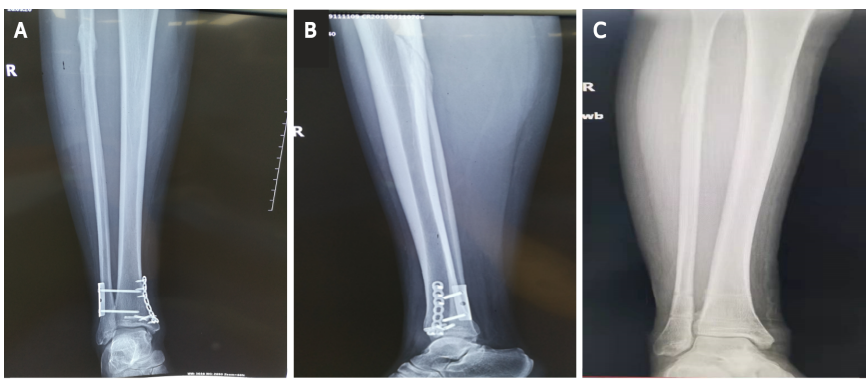

图片

图4:术后3个月的踝关节和小腿X线片。A、B:拆除内固定前踝关节及小腿正位及侧位X线片;C:拆除内固定后踝关节及小腿正位X线片